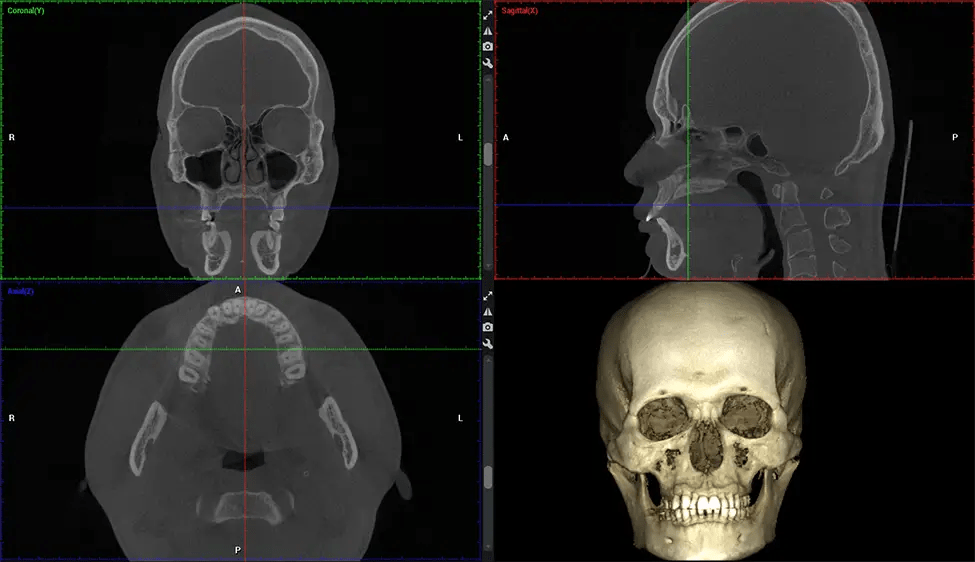

Cone Beam Computed Tomography (CBCT) is an advanced imaging technique used in dentistry and maxillofacial surgery to obtain detailed 3D images of the oral and maxillofacial structures. At Dr G Dental Studio, our CBCT scanners utilize a cone-shaped X-ray beam and a specialized detector to capture images from different angles. A computer then combines these images to create a 3D representation of the patient’s oral anatomy.

This 3D scan, called cone beam computed tomography, gives your dentist a more complete image of your oral anatomy and disease processes than a traditional X-ray. Unlike conventional X-rays, which capture a 2D image of your mouth from various angles, a 3D scan takes multiple digital X-rays for one image. It provides a complete view of your jaw, teeth, nerves, and soft tissues. This enhanced view allows dentists to detect minor issues not visible in traditional 2D scans, such as impacted wisdom teeth or bone fractures in the sinus cavity.

There are many benefits to using CBCT technology, especially compared to the traditional 2D X-ray format. One of the most significant advantages of CBCT scans is that they provide much more information than traditional X-rays. A scan lets your dentist see images from all angles of your jaw and mouth, including your sinuses, nasal cavity, cheekbones, and other surrounding areas. This added information helps your dentist craft a comprehensive treatment plan that addresses all aspects of your oral health.

The patient is first positioned in the CBCT scanner, which typically consists of a rotating arm that houses the X-ray source and a detector. The patient’s head is immobilized to ensure accurate image capture. The X-ray source and detector rotate around the patient’s head, capturing various X-ray images from multiple angles. As the X-ray source rotates, it emits the cone-shaped X-ray beam towards the detector. The detector captures the X-ray images, which are then processed by the CBCT software.

After the scanning process, the captured X-ray images are processed by the CBCT software, which applies algorithms to reconstruct a detailed 3D image of the scanned area. The software compiles these individual X-ray images and creates a digital 3D representation of the patient’s anatomy. The reconstructed 3D CBCT image can be viewed and analyzed by the dentist or radiologist. This image can be manipulated, rotated, and zoomed in or out to examine specific structures and evaluate the patient’s condition.

Planmeca Viso G7 CBCT ( Cone Beam CT Scan ) is designed to surpass the demands of industry leaders, specialists, and large institutions. It’s has a large ø25×30 cm sensor with four built-in cameras. It can capture unlimited volume sizes from a ø3×3 cm to a ø30x30cm volume capturing the skullcap through C7 on the cervical spine. The Planmeca Viso G7 offers the industry’s largest single volume scan of ø30×19 cm. It’s poised to handle advanced imaging modalities such as Planmeca ProFace® and Planmeca 4D™ Jaw Motion technology. The occipital head support allows an unimpeded view of facial tissue.